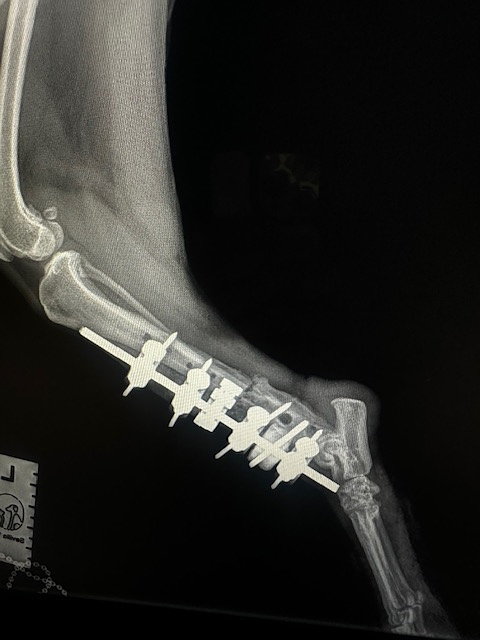

This 6-yr old boy we named River, was hit by a car in Anaheim and found himself at the OC Animal Shelter with a broken leg and unable to urinate or defecate on his own for 72 hours.

Facing euthanasia, SAFE Rescue Team came up with a plan! We picked him up and transported him to our amazing orthopedic Smart Approach Veterinary Services in Santa Monica for emergency surgery.

The x-rays showed not only did River have a fractured rear left leg, he had multiple broken ribs and a dislocated/twisted front right shoulder. River's veterinary bills have exceeded over $7,000 and we need your help! 🙏🙏🙏